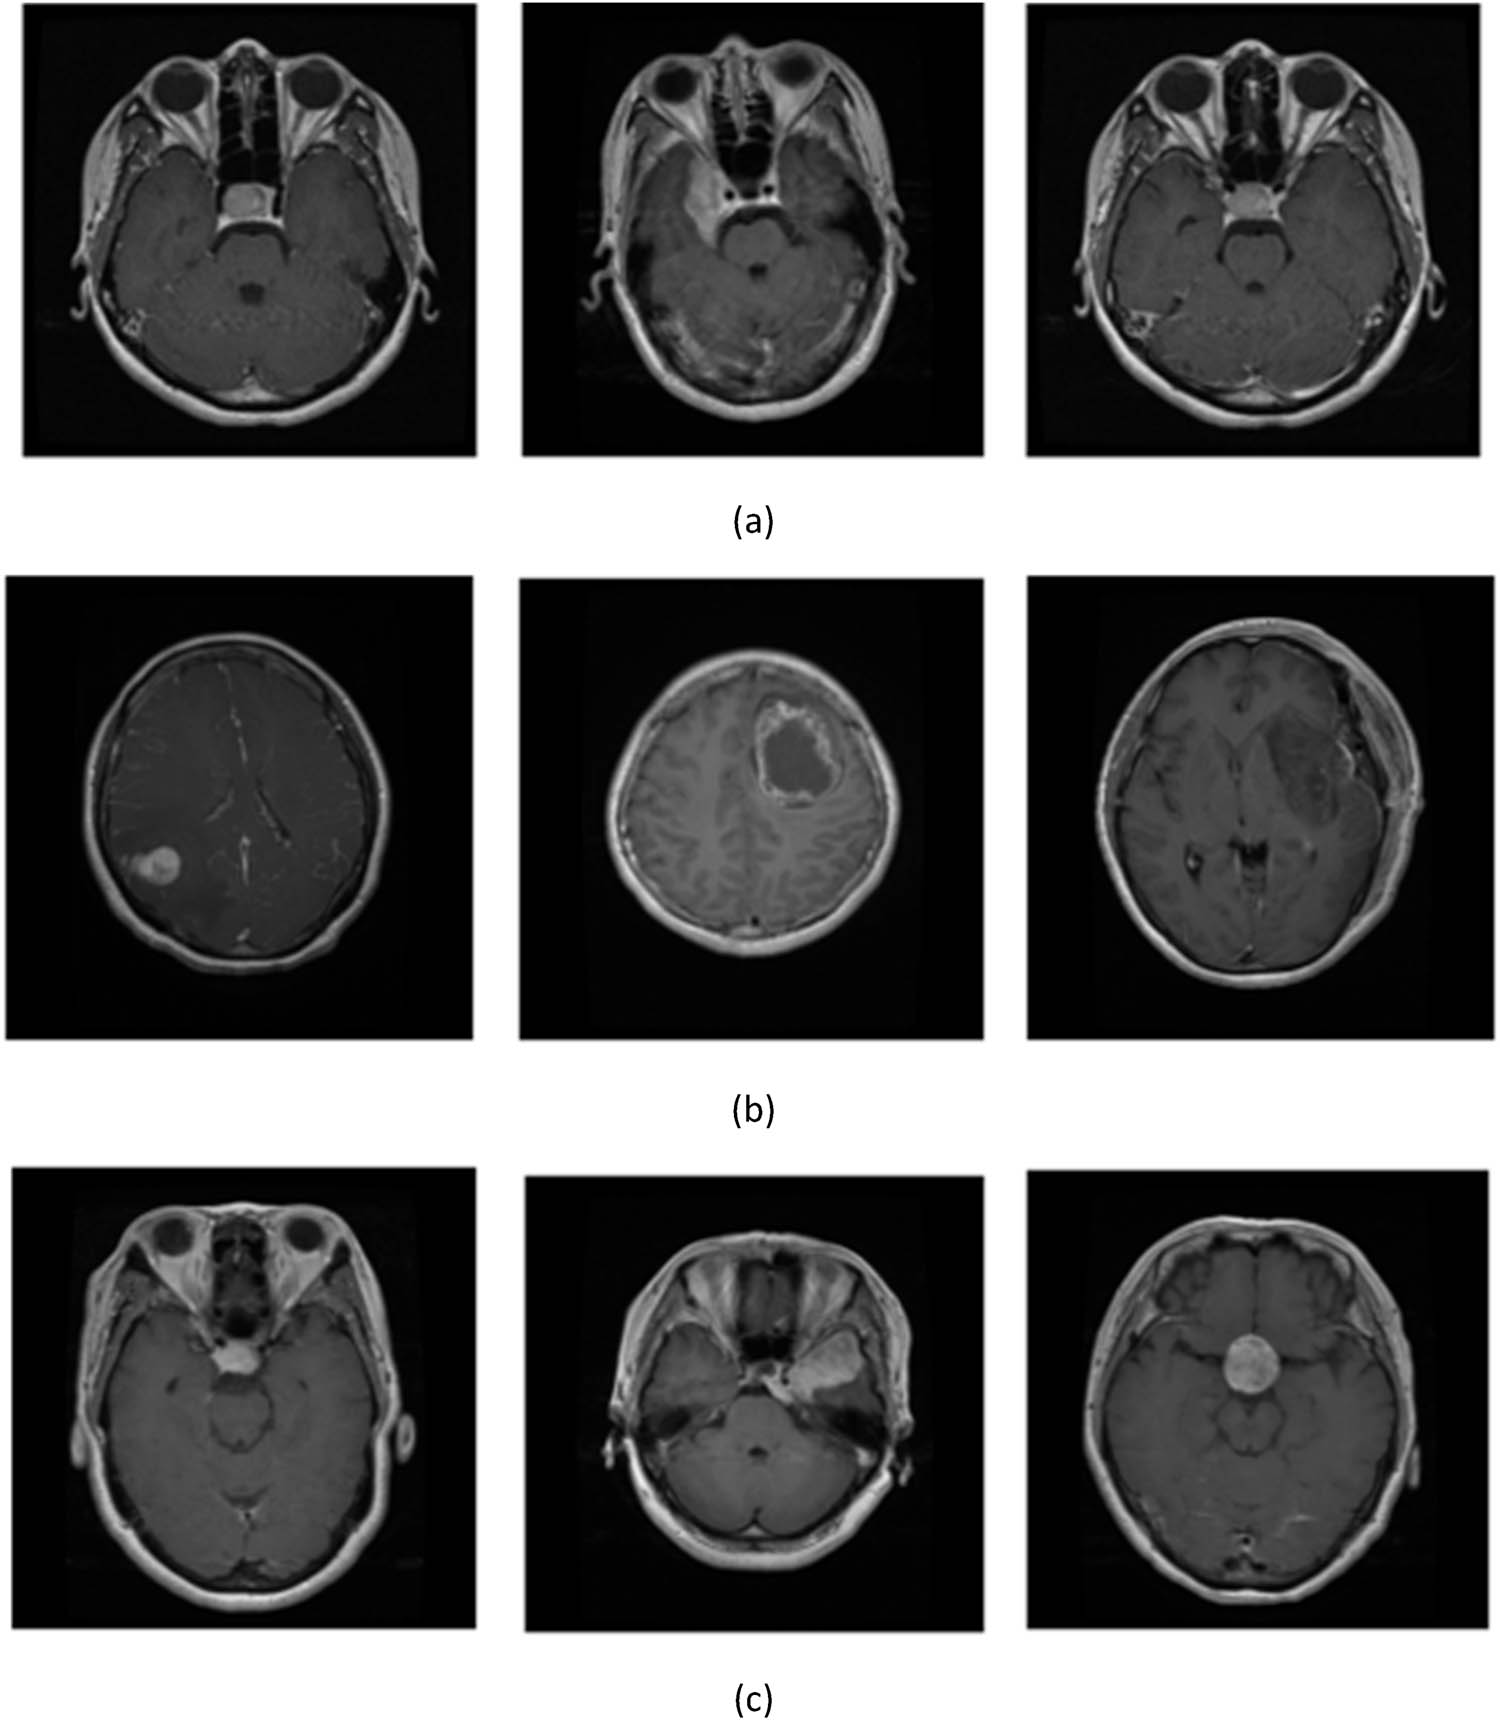

Figure 4

Sample images of (a) pituitary, (b) glioma, and (c) meningioma.